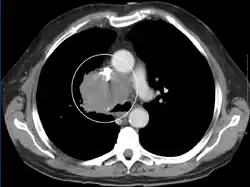

A CT image showing compression of the right hilar structures by cancer

The main techniques of diagnosing SVCS are with chest X-rays (CXR), CT scans, transbronchial needle aspiration at bronchoscopy and mediastinoscopy.[6] CXRs often provide the ability to show mediastinal widening and may show the presenting primary cause of SVCS.[6] However, 16% of people with SVC syndrome have a normal chest X-ray. CT scans should be contrast enhanced and be taken on the neck, chest, lower abdomen, and pelvis.[6] They may also show the underlying cause and the extent to which the disease has progressed.[6]